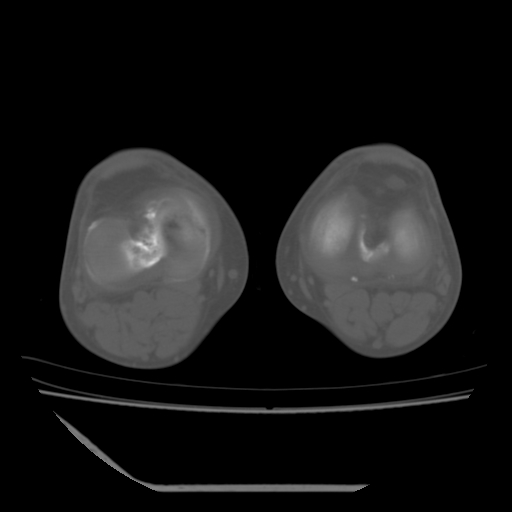

这是由于两侧的肌肉不对称所致,加上扫描的平面也有些差异。请看示意图:

这个病例诊断:退行性骨关节炎